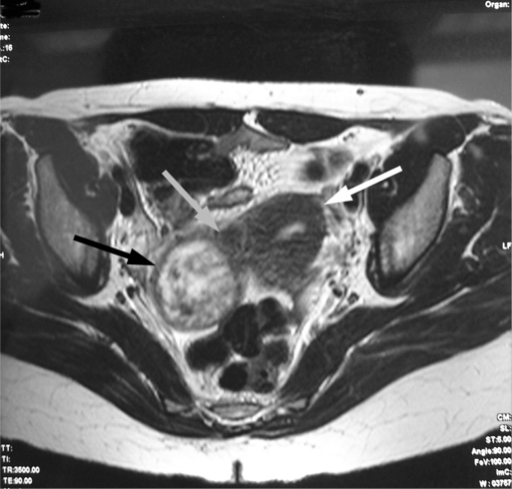

残角子宫妊娠